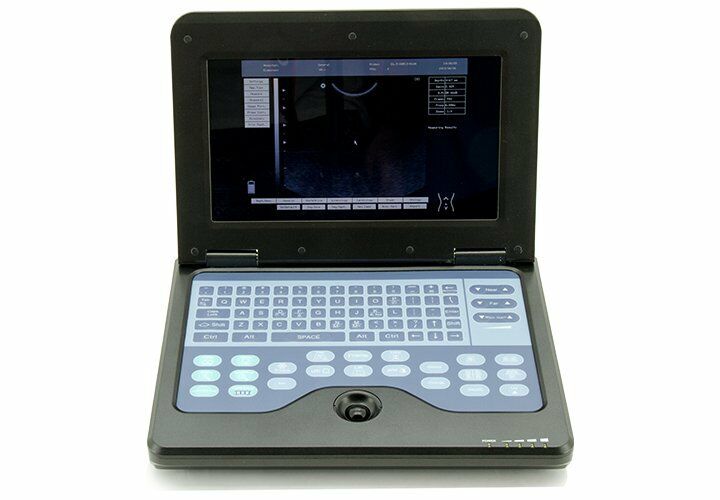

When it comes to advanced diagnostic tools, the Newest Digital Portable Laptop Ultrasound Scanner stands out. This compact and efficient device is designed to provide high-resolution images, making it an essential tool for medical professionals. The 7.5MHz Linear probe ensures detailed imaging capabilities, which can be critical in various medical examinations.

The Newest Digital Portable Laptop Ultrasound Scanner is not just about high-quality imaging but also about user convenience. The device is equipped with intuitive software that simplifies the diagnostic process. Medical practitioners can store and retrieve patient data efficiently, and the scanner supports various imaging modes for different diagnostic needs. This versatility makes it a valuable asset in any healthcare setting, from hospitals to private clinics.